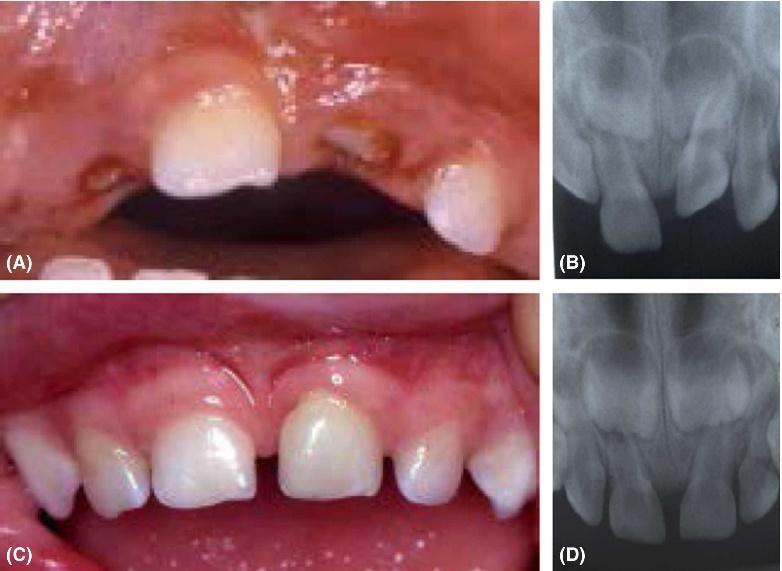

Στην συγκεκριμένη περίπτωση η παρουσία οδοντωμάτων εμποδίζει την ανατολή των μόνιμων κεντρικών τομέων καθιστώντας τα έγκλειστα.

H έγκαιρη παρέμβαση λύνει το πρόβλημα με την χειρουργική απομάκρυνση των οδοντομάτων και με την υποβοηθούμενη μετατόπιση των κυρίως δοντιών με ορθοδοντικές δυνάμεις.